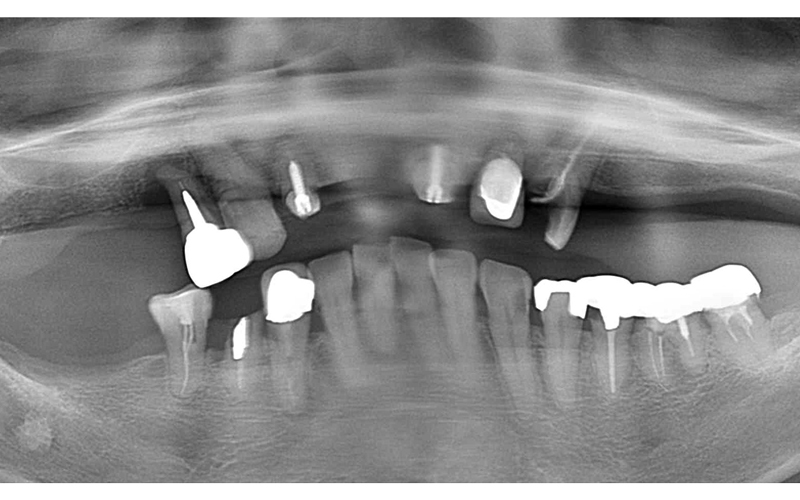

奥歯で噛めない方へのインプラント症例

Before

After

| 主訴 | 奥歯で噛めない・入れ歯が合わない |

|---|---|

| 年齢・性別 | 72歳・女性 |

| 治療期間・回数 | 10ヶ月(他の治療も同時進行) |

| 治療方法 | 骨造成・インプラント埋入 |

| 費用 | 合計:1,498,000円(骨造成を含む) |

| デメリット・注意点 | 自費診療のため費用がかかる。定期メンテナンスが必要。 |

| 備考 | 初診時、以前義歯を製作して貰ったみたいですが使用しておらず、奥歯で咬んでいない状態で来院。前歯が前方に出ているのが気になるとの事でした。 右上の端の歯は根の病変で保存不可能の状態でした。前歯の治療を含め奥歯にインプラント治療を選択しました。 |